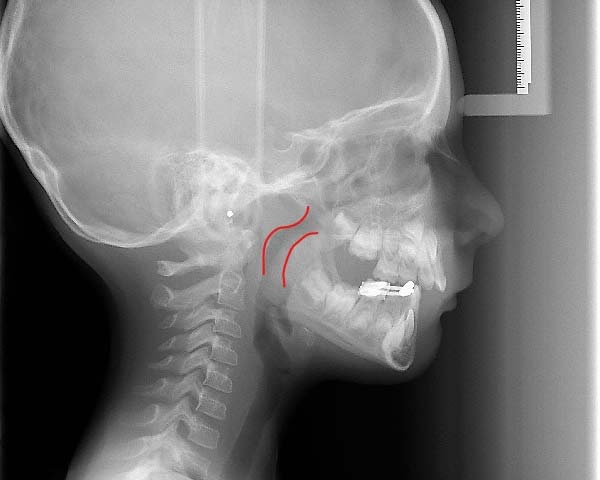

The best age is as soon as it is suspected there are airway issues, our youngest patient is 2.5 years old. The sooner we recognize an airway issue, the greater the chances of achieving harmonious physical and neural growth and development. Below are examples of patients in our practice who have undergone airway development for pediatric sleep apnea or sleep disordered breathing:Adults